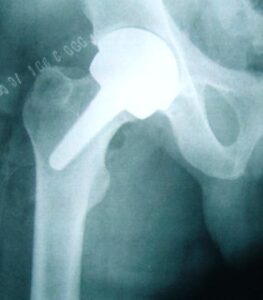

– Anca, ginocchio, spalla: sono sempre di più gli italiani “bionici”, che utilizzano “pezzi di ricambio” per sostituire articolazioni non più al meglio e deteriorate dal tempo.

Superano il milione i pazienti che hanno ricevuto una protesi articolare e sono 180mila ogni anno i nuovi impianti di protesi per anca, ginocchio, spalla o altre articolazioni, oltre la metà eseguiti in Lombardia e in Emilia Romagna anche a causa della mobilità sanitaria tra le Regioni. Nel 60% dei casi si tratta di protesi d’anca, ma crescono a ritmo vertiginoso anche le sostituzioni di ginocchio.

Nel mondo si impiantano un milione e mezzo di protesi d’anca ogni anno, di cui 300.000 negli Stati Uniti; l’Italia è fra i Paesi europei dove si effettua il maggior numero di sostituzioni d’anca. Su circa 700.000 interventi eseguiti ogni anno in Europa, infatti, oltre centomila riguardano il nostro Paese, che è superato soltanto da Germania (250.000) e Francia (130.000). Nel 65% dei casi la sostituzione dell’anca riguarda le donne, e la percentuale sale al 75% se l’impianto è successivo a una frattura da osteoporosi.